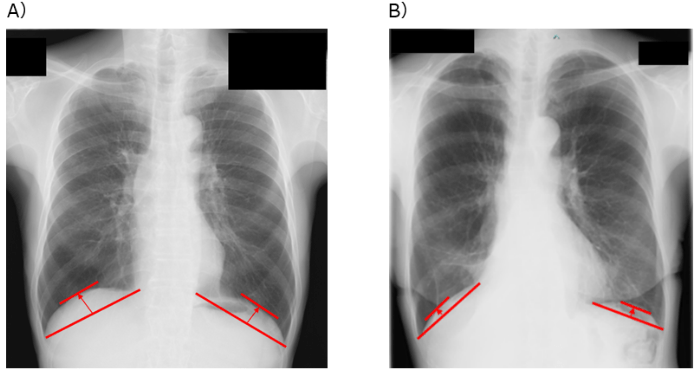

A)胸部X線画像による、横隔膜ドーム高の測定方法、B)横隔膜ドーム高が低い患者の例

そこで研究グループは、胸部X線画像から簡便に測定できる横隔膜の位置の高さである「横隔膜ドーム高※3」という指標に注目しました。横隔膜ドーム高は、肺機能や運動耐容能と密接に関連することが明らかになっており、より簡便かつ患者に負担なく術後予後を予測する指標となる可能性があります。しかし、これまで肺がん患者において、横隔膜ドーム高と術後の予後との関連性は明らかにされていませんでした。

※3 横隔膜ドーム高:横隔膜がどれくらい上に持ち上がっているか(高さ)を示す指標。